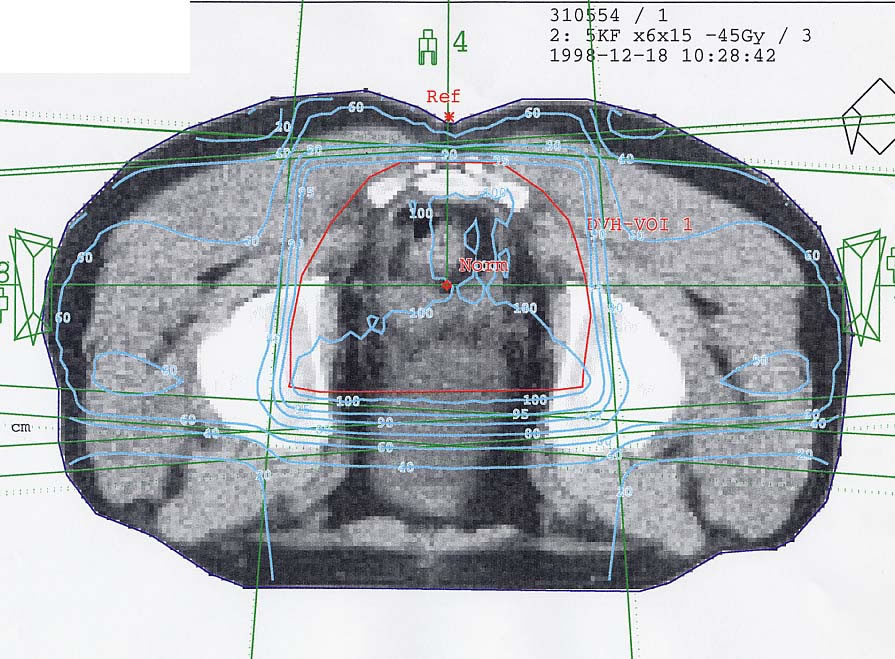

Rektumkarzinom (Enddarm): Bestrahlungsplan

Bestrahlungspläne